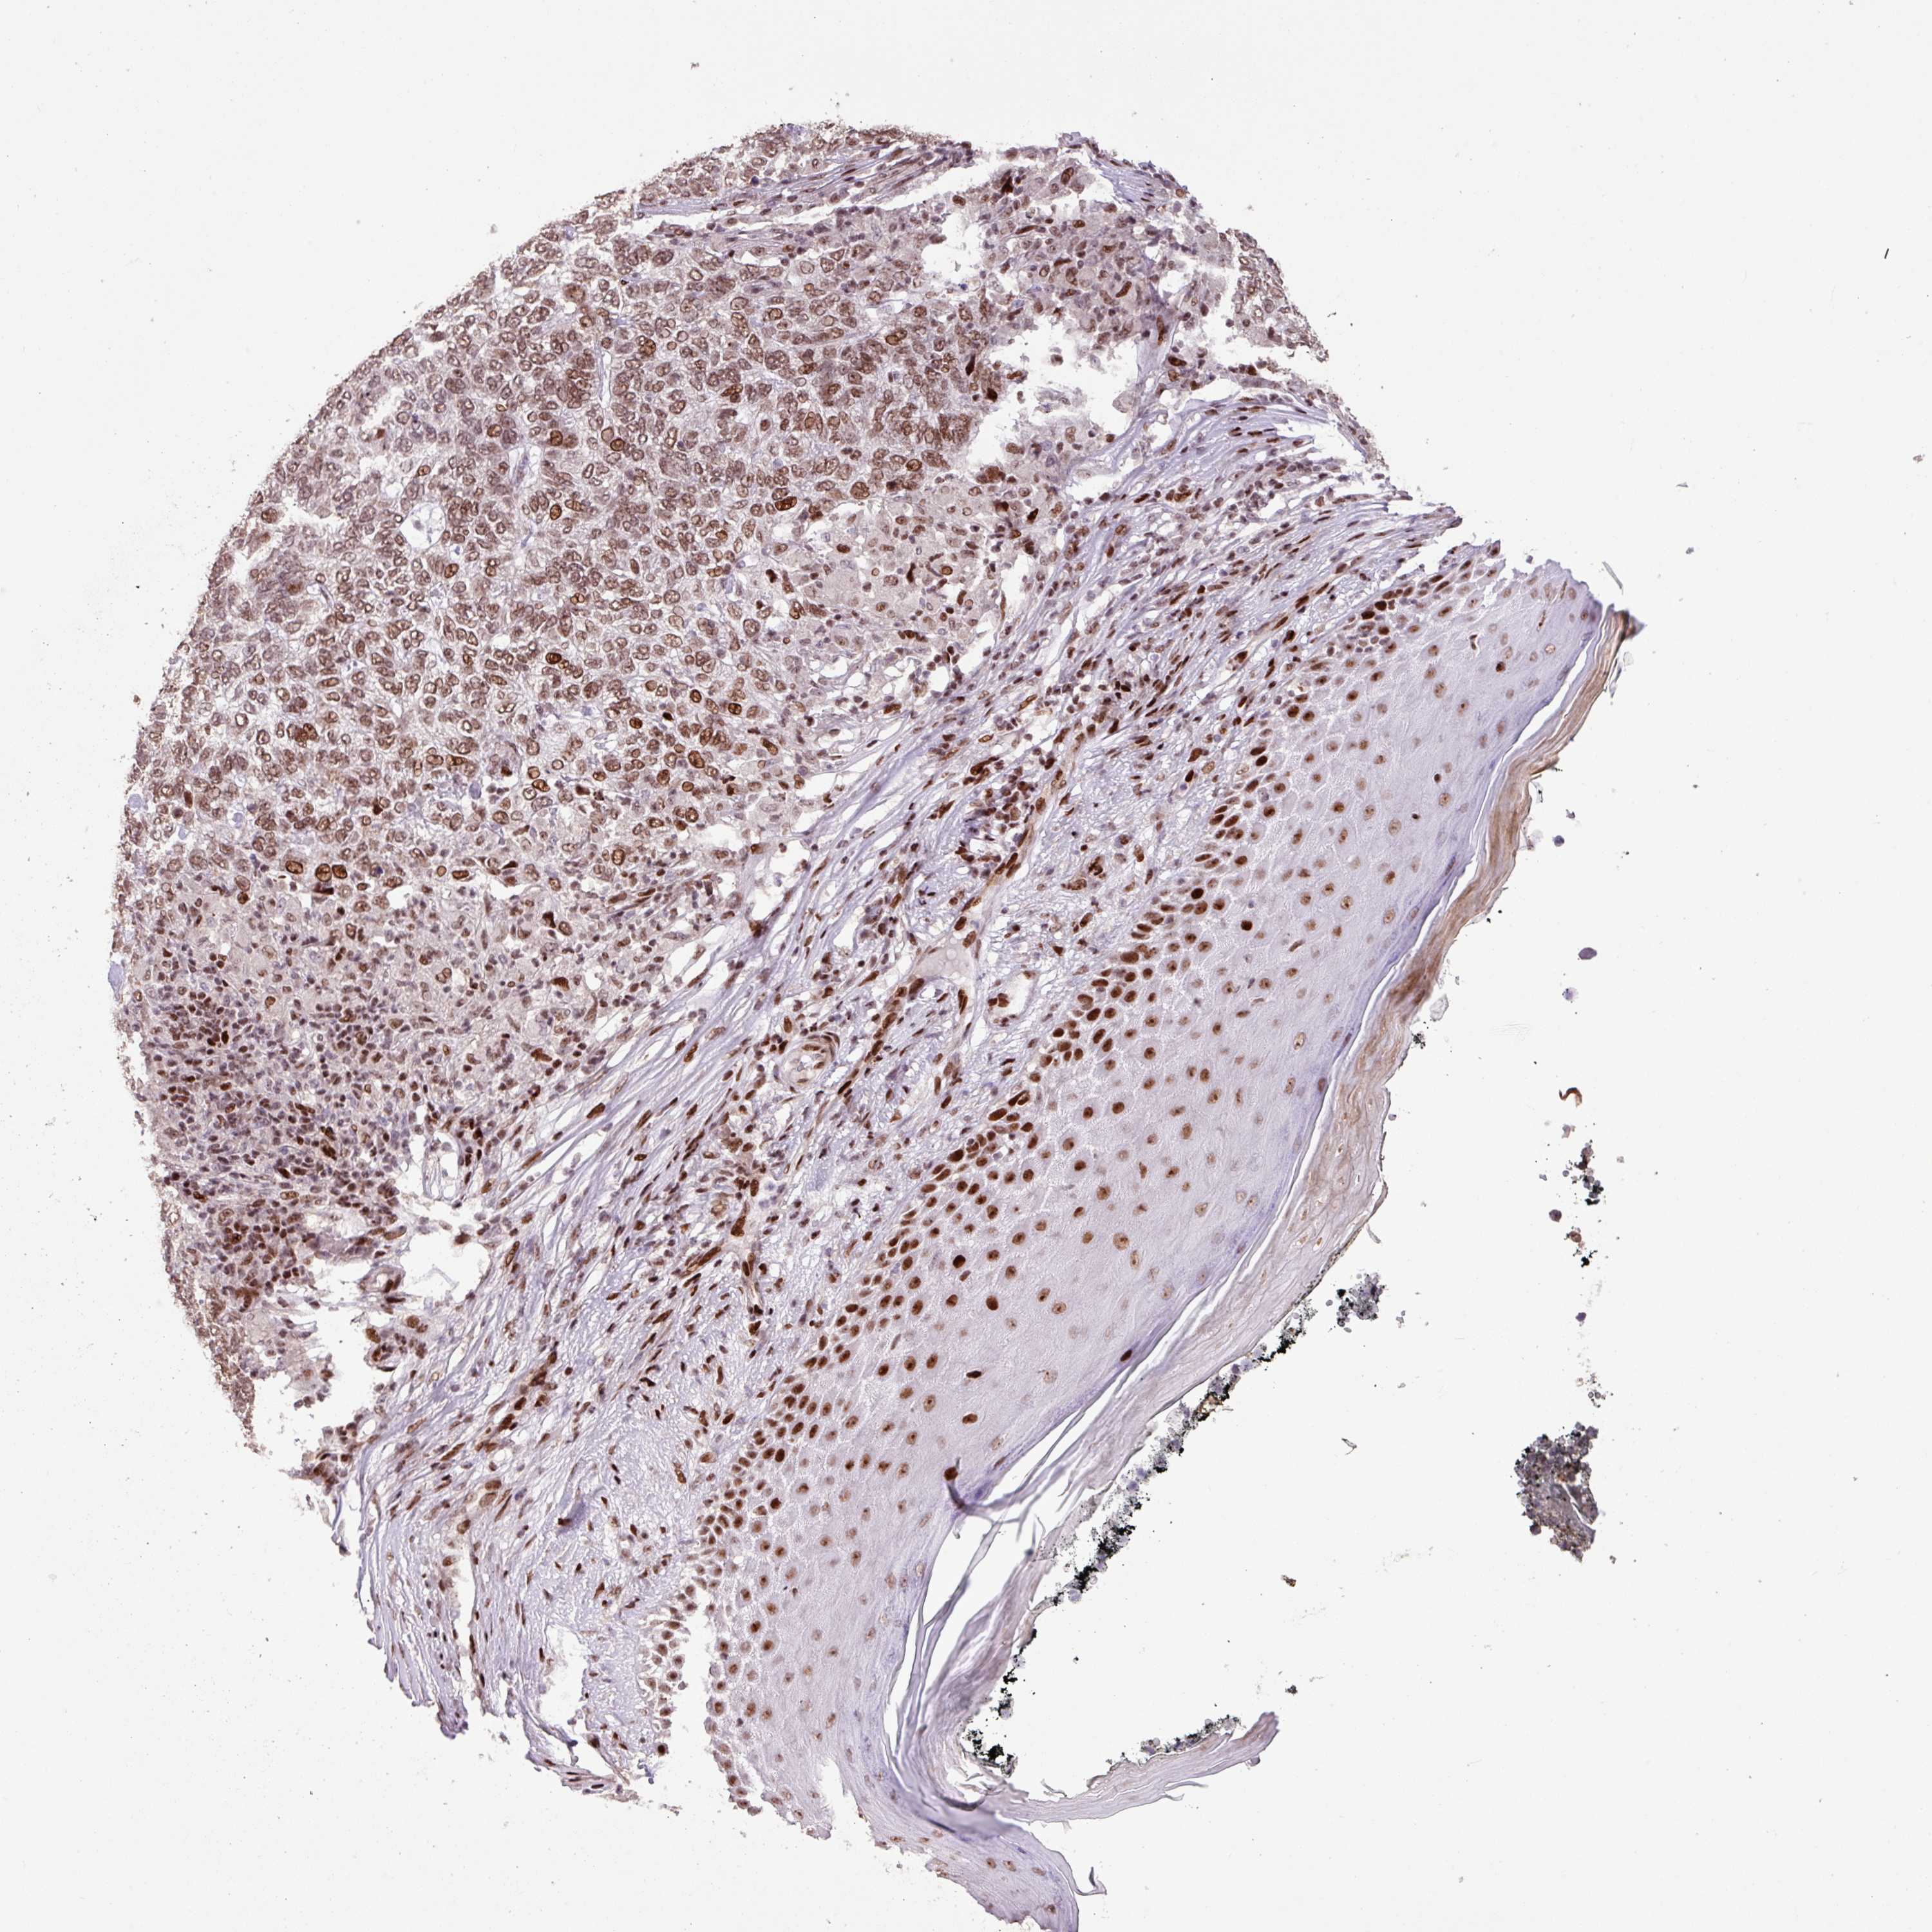

CANCER SKIN CANCER Show tissue menu

Basal cell and squamous cell cancer

SKIN CANCER - Protein expressioni

A mouse-over function shows sample information and annotation data. Click on an image to view it in a full screen mode. Samples can be filtered based on level of antibody staining by selecting one or several of the following categories: high, medium, low and not detected. The assay and annotation is described here.

Each image is clickable and will lead to virtual microscopy that enables deeper exploration of all samples and also displays staining intensity scores, fraction scores and subcellular localization as well as patient and tissue information for each sample.

Antibody HPA053153

Staining

High

Intensity

Strong

Quantity

>75%

Location

Nuclear

Basal cell carcinoma

Squamous cell carcinoma, NOS

Squamous cell carcinoma, metastatic, NOS